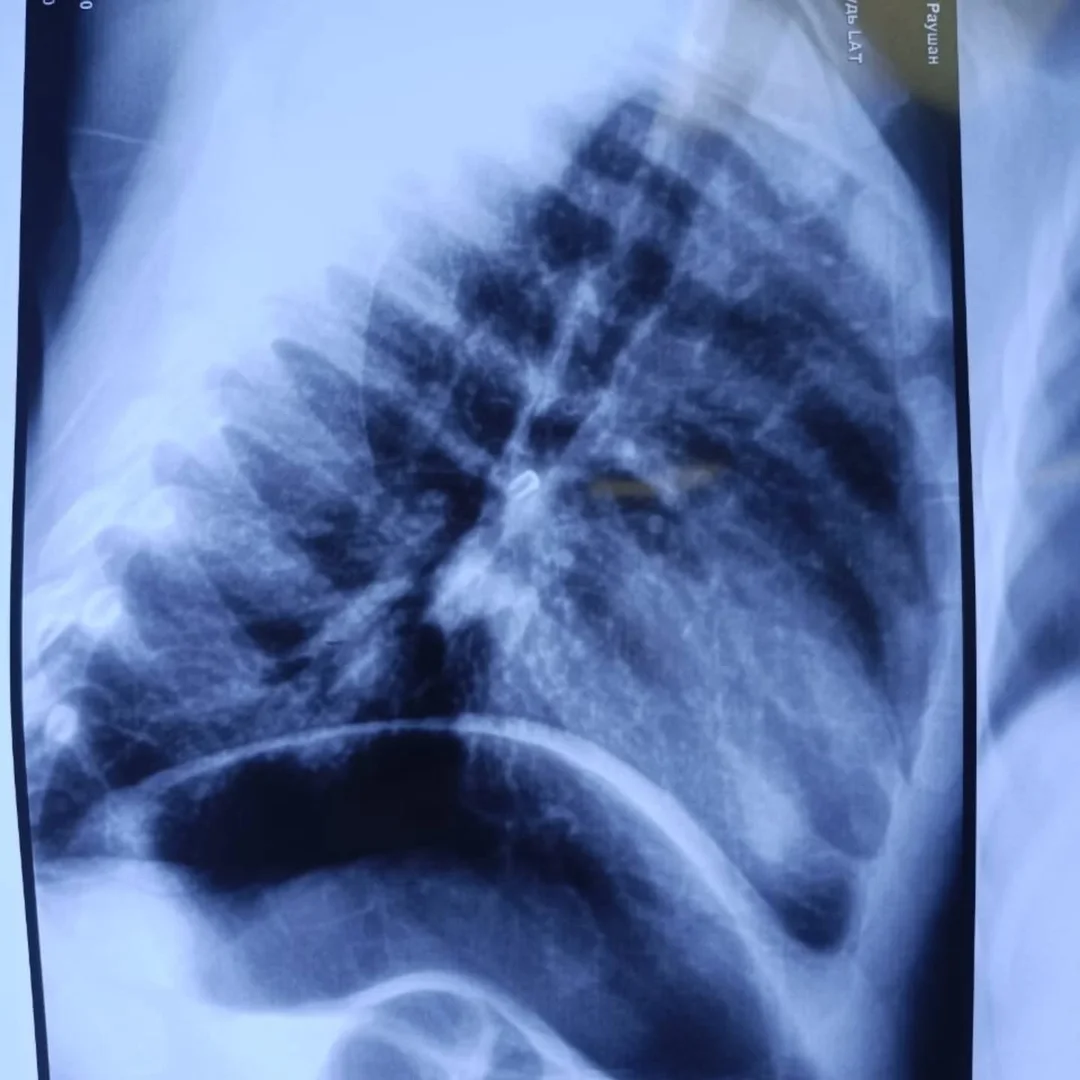

При поступлении состояние малыша оценивалось как тяжелое из-за дыхательной недостаточности. Рентгенография показала инородное тело в проекции правого главного бронха.